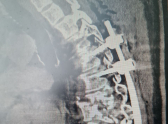

Хирурги выполнили транспедикулярную фиксацию (ТПФ) на уровне 5-6-го и 9-10-го грудных позвонков. Это современный метод стабилизации, при котором в тела позвонков через их ножки вводятся специальные импланты - титановые винты.

Ювелирная точность установки этих винтов стала возможной благодаря использованию навигационной станции и операционного микроскопа. После того как винты были установлены, врачи смонтировали металлоконструкцию, которая надежно зафиксировала сломанные позвонки, восстановив анатомически правильную ось позвоночника и полностью устранив угрозу для спинного мозга.